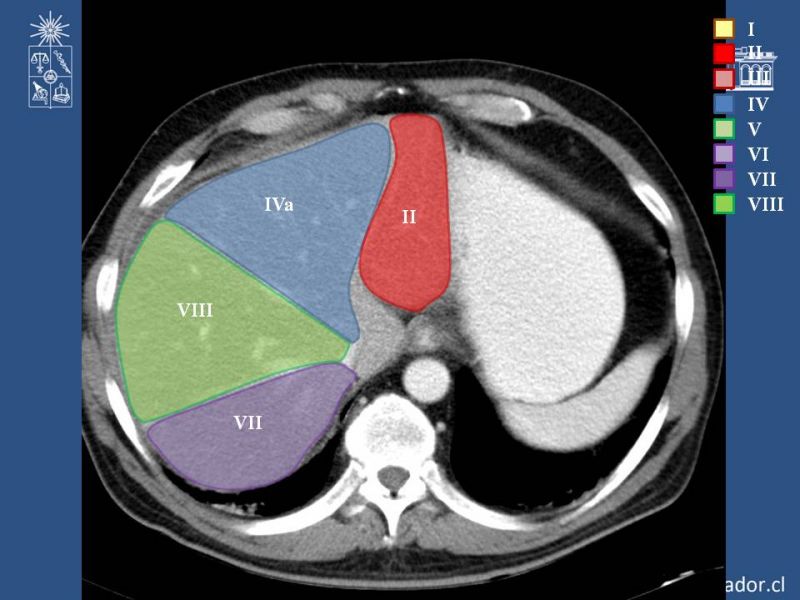

Anatomía Hepática

Hepatobiliopancreático

| Autor: Dr. Enrique Aguila Reyes